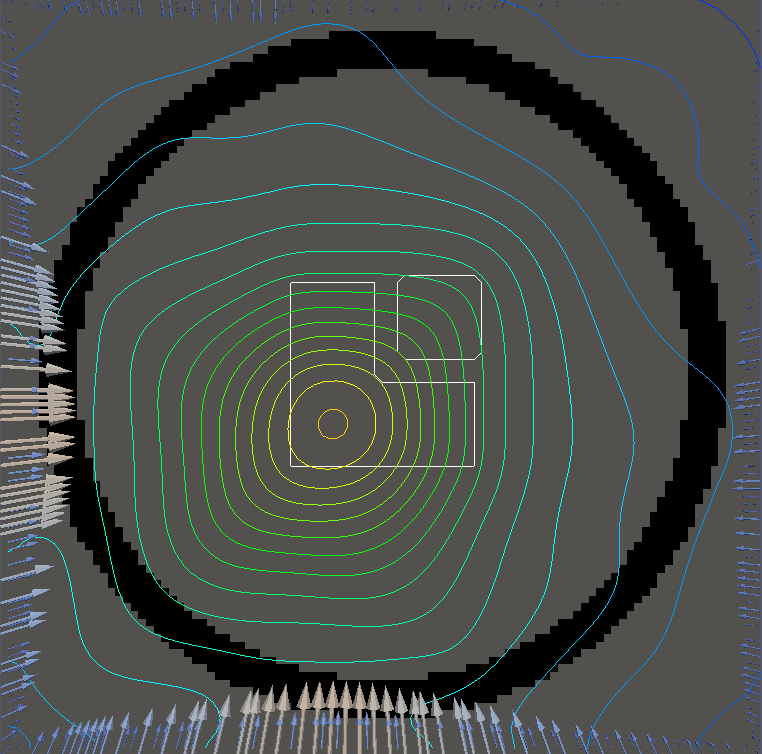

For testing, we use three tumor/risk region regions similar to those in [13]. Specifically, we define the regions in Table 3 and are shown in Figure 1; the void region is shown in black and the tumor and risk regions are traced in white. In the basic target case, seen in Figure 1(a), the tumor region is a box, as is the risk region. The second, intermediate target case, seen in Figure 1(b), involves an L-shaped tumor around a box-shaped risk region. Finally, the complex target case in Figure 1(c) involves a C-shaped tumor around a risk region.

Figure 2 shows the optimal boundary source term for both and The vectors shown on the boundary are the time-integrated values of normalized and then scaled by In Figures 2(a), 2(c), and 2(e) (corresponding to ), the isolines are spaced at intervals of the maximum of the desired dose (here, 5). In the intermediate and tracking cases, we see that relatively low dose levels are attained, primarily due to the high penalty to any dose deposited in the risk region. In Figures 2(b), 2(d), and 2(f)(corresponding to ), the isolines are spaced at intervals of of cells killed. Here a high proportion of the tumor cells are killed (in each case ) while in the Intermediate and Basic cases, the tumor has at least survival; in the Complex case, the risk region has survival.